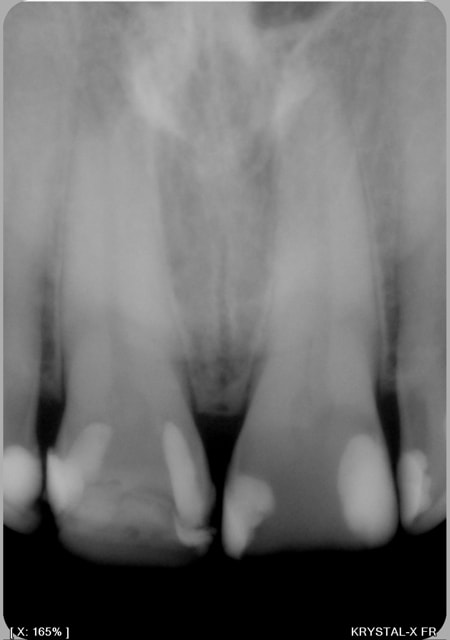

pour comparaisons , voici deux images; l'une capteur kodak 6100 l'Autre julie Krystal X

11 21 afetr5 - Eugenol

029 athojb - Eugenol

dentiste57 écrivait:

> pour comparaisons , voici deux images; l'une capteur kodak 6100 l'Autre julie

> Krystal X

L'image du 6100 est traitée à mort...

Pour comparaison, voici l'image du Krystal X traitée à la truelle, tu conviendras que le résultat approche pas mal de celle du 6100. Avec des données brutes du capteur du Krystal X et des conditions de prise de vue identiques pour les deux images, le résultat serait très approchant, amha.

029edit3 p6ae0c - Eugenol

> > pour comparaisons , voici deux images; l'une capteur kodak 6100 l'Autre julie

> > Krystal X

he ben non !

l'image du 6100 est brute de fonderie comme celle du krystal x.

regarde un peu plus prés les détails et les niveaux de gris sur le 6100.

il y a une nette différence pour moi; au moins celle de ne pas devoir corriger mes images avec photoshop...

Elle est traitée par le logiciel !

Et pour moi, elle est surtraitée... Ca fait apparaître un halo radioclair autour de chaque obturation qui n'est qu'un artefact de la sharpenisation.

Oui, mais je me permet juste de préciser qu'on préfère toujours l'image la plus traitée parce que c'est plus plaisant au premier abord, mais ce n'est pas forcément la plus fidèle.